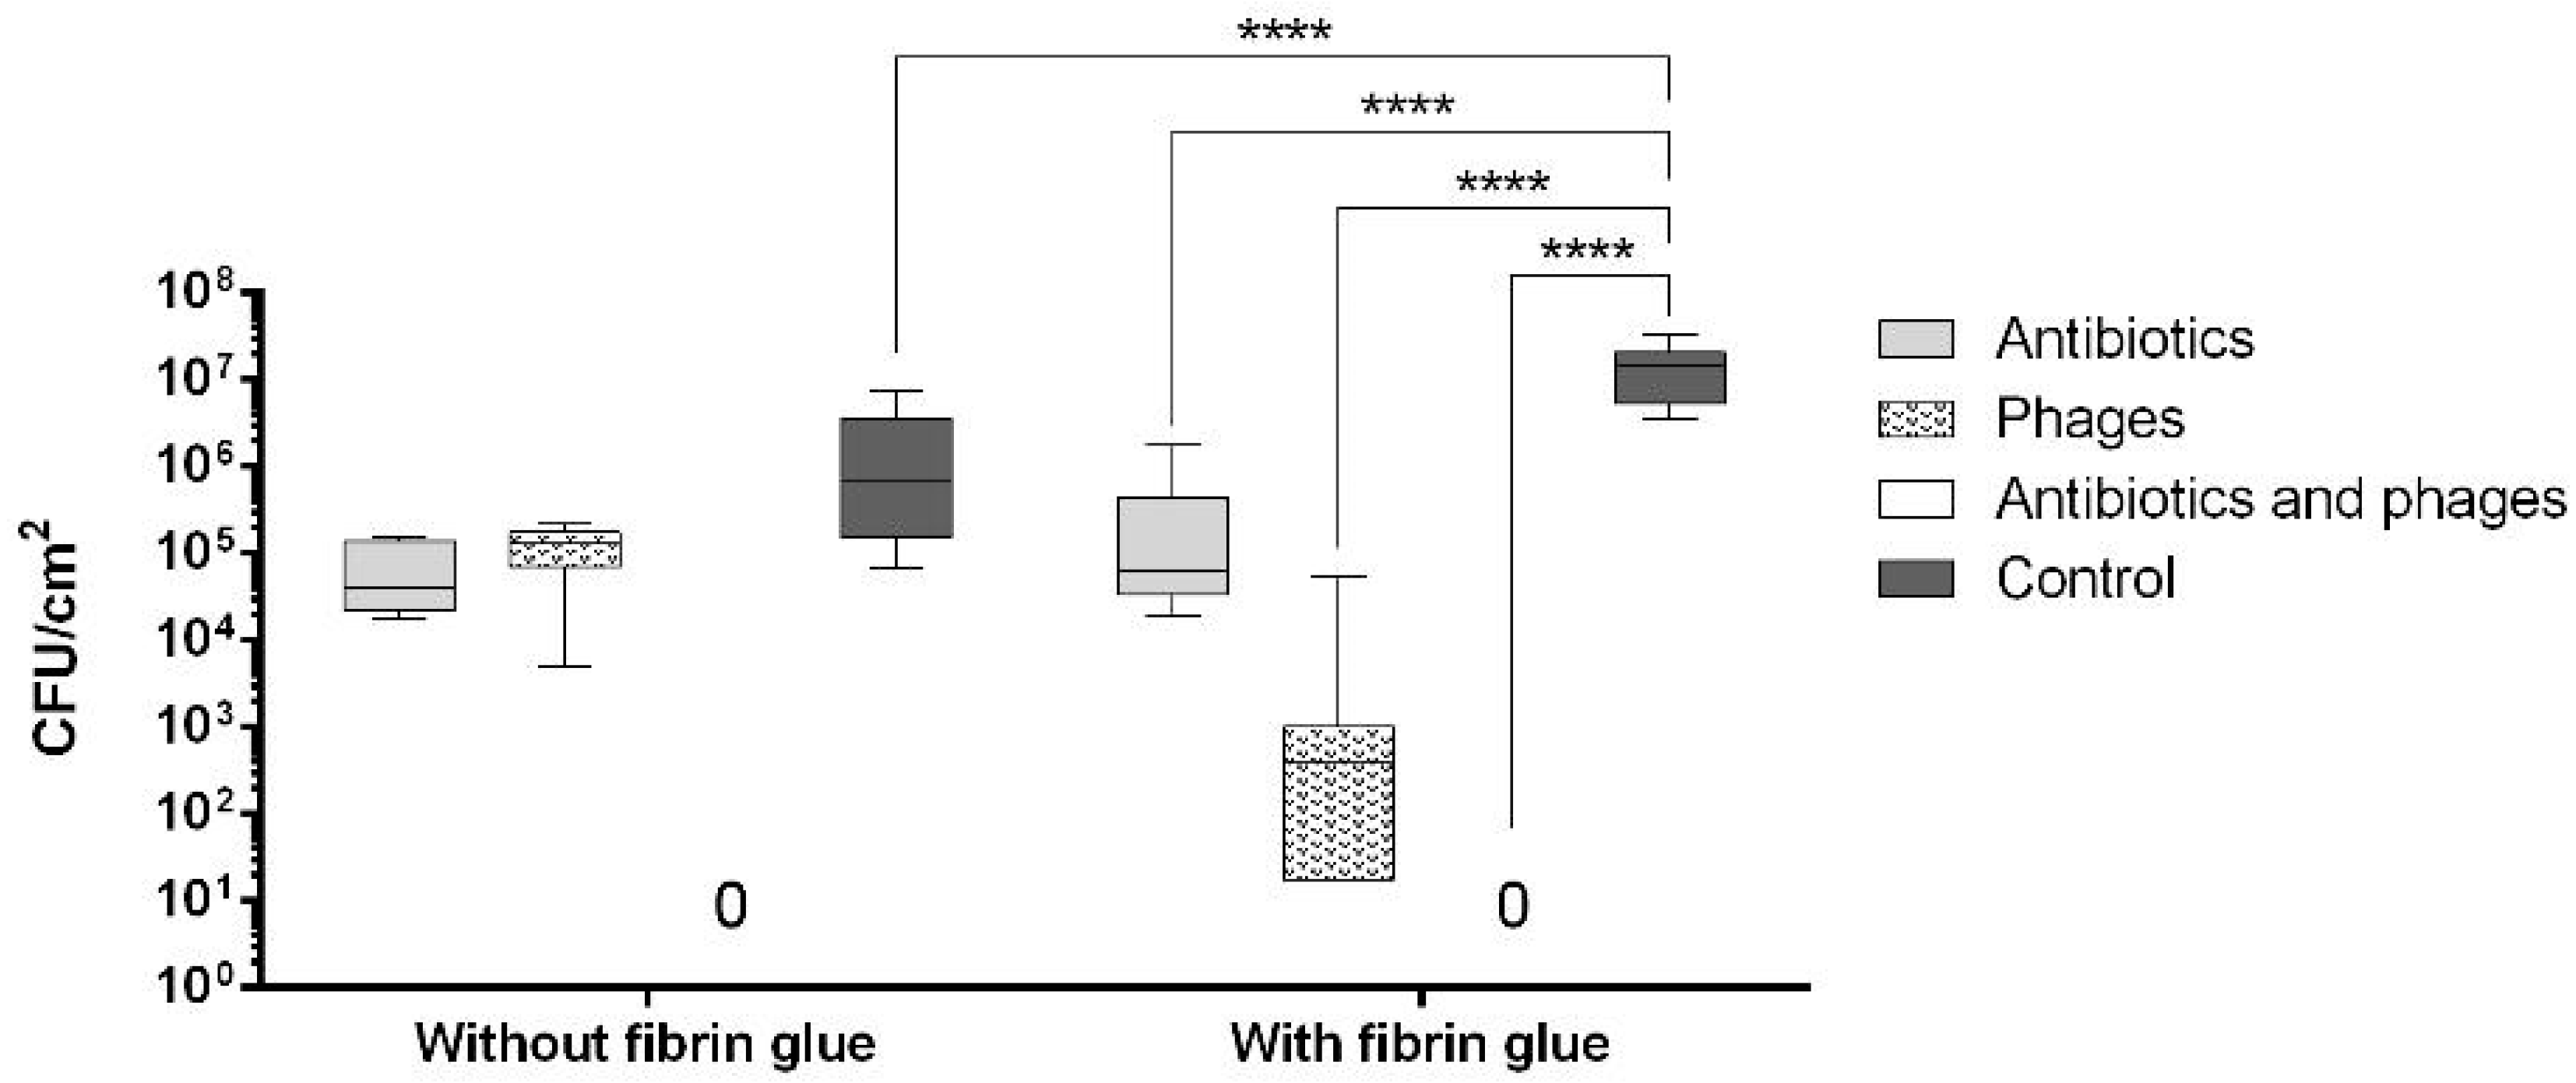

2.2. Antibacterial Loads of Graft Samples

2.2.1. Uncoated Grafts

2.2.2. Coated Grafts

2.3. Antibacterial Activity against Single Contamination

2.3.1. Activity against Staphylococcus aureus

2.3.2. Activity against Escherichia coli